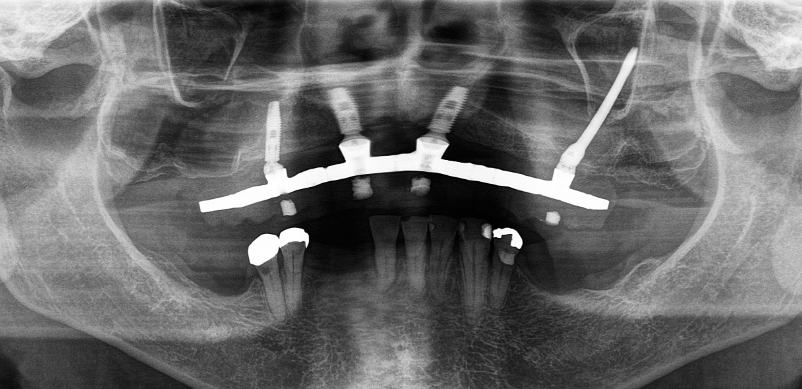

Por que o dentista pede tomografia antes de implantes dentários

A tomografia computadorizada odontológica permite visualizar a anatomia tridimensional da face. Enquanto uma radiografia mostra uma foto, a tomografia mostra o filme completo, em 3D.

- Visualizar a profundidade exata do osso;

- Planejar a posição ideal do implante com segurança;

- Simular a cirurgia virtualmente;

- Avaliar se há necessidade de enxerto ou se técnicas avançadas (como implantes zigomáticos) são viáveis.